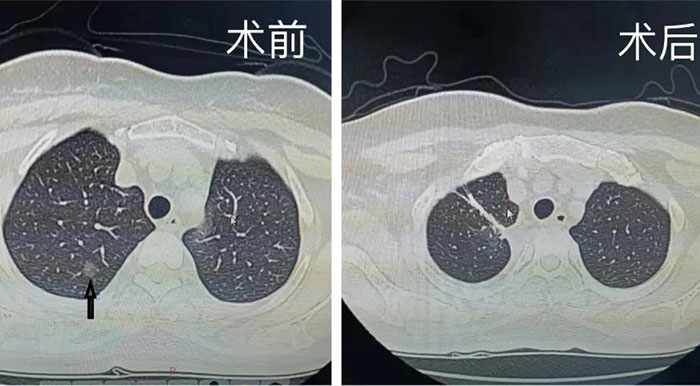

北京胸科医院胸外科成功切除一巨…

日前,一例长在胸腹腔的巨大肿瘤在北京胸科医院被成功切除。这个足足15斤重,大如足球的肿瘤,在医院微创中心医生的细心手术下,历时四个小时,惊现“真身”,这也让被它长时间困扰的白女士重获新生。三个…